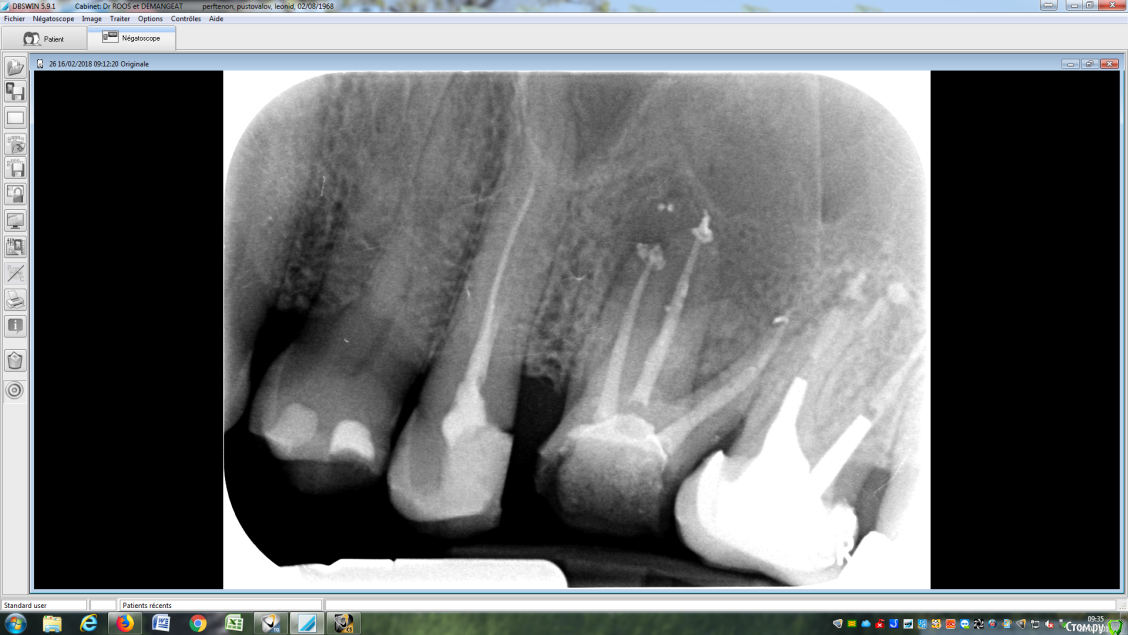

LeoRuss Опубликовано 20 февраля, 2018 Поделиться Опубликовано 20 февраля, 2018 (изменено) Здравствуйте уважаемые метры, в очередной раз обращаюсь к вам за советом.Чуть меньше года назад эндодонтическим методом в полном соответствии с вашими рекомендациями была пролечена киста 26.( http://forum.stom.ru/topic/34508-podsadka-kosti-pri-kiste-nuzhna-li-v-dannom-slucha/ ) При вскрытии зуба выявилась неприятная картина: оба титановых штифта в далеком ‘94м были завернуты мимо корневых каналов прямо в челюсть ;(Док все демонтировал, прочистил под микроскопом и каналы и дыры от штифтов и замуровал МТА : спустя 8 месяцев - 10/2017 : И вроде бы все чудесно, но пару раз за это время десна вокруг зуба воспалялась, и зуб становился более подвижным, но все проходило после 2-3-5 дневного интенсивного полоскания хлоргексидином. Три недели назад была наконец то установлена коронка на соседний 27й, десна с внутренней стороны 26ки тогда была тоже припухшей и протезист посоветовал сходить на контроль к эндодонтисту. Напросился и сходил через неделю, десна за это время еще чуть распухла (только со стороны языка), стало больно при легком нажатии на десну в районе верхушки корня ближнего к 25ке и при покачивании зуба. Док сделал снимок, сказал что все чисто и он понятия не имеет почему все надулось. Вариант удаления забраковал, сказал что по его мнению все хорошо, и можно уже ставить коронку. А вот в импланте смысла никакого, тем более что кости для него пока недостаточно, тк межкорневая область еще не дозаросла. Посоветовал терпеть и.. поставить коронку, тк нагрузка на зуб при жевании должна активировать заживление.Но жевать на этой стороне я стал почти месяц назад, сразу после установки временной коронки на 27, вот с тех пор с 26кой все хуже и хуже. За последние полнедели опухоль сильно увеличилась, и между 25/26, и в сторону нёба, дергает в ритме пульса. Появились отголоски боли в носоглотке и в заглазье.Терпеть уже плохо получается, да и смысла не вижу. Вижу два варианта:1. Удалять 26 чтоб не мучаться, с последующей имплантацией, но как быть с нехваткой кости?2. Вскрыть каналы и прочистить еще раз, но даст ли это хоть что то, да и возможно ли в принципе? В любом случае хотел бы узнать ваше мнение, спасибо ! Изменено 20 февраля, 2018 пользователем LeoRuss Ссылка на комментарий